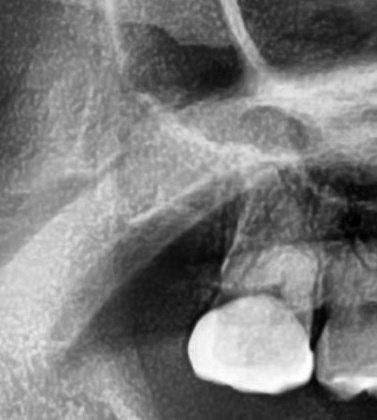

パノラマ写真を撮影してみると、右上の親知らずは手前の歯と並んでまっすぐ生えているのが確認できました。

今回は上顎洞からも距離があるため、抜歯は可能と診断されました。